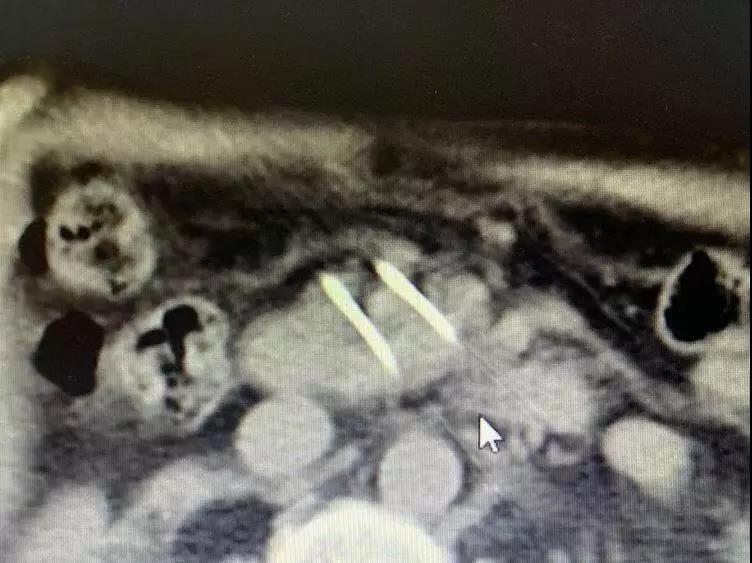

Необратимая электропорация при опухоли поджелудочной железы

Для дальнейшего лечения как можно скорее его сын привез его в Онкологическую больницу Фуда 31 августа. После обследования ему был поставлен диагноз несоциализированная аденокарцинома III стадии в поджелудочной железе и диабет II типа с множественными узлами в печени, легких и щитовидной железе. После обсуждения с доктором Ню Личжи и медицинской командой он и его семья согласились провести катетеризацию в подключичной вене 6 сентября и на сдедующий день необратимую электропорацию при опухоли поджелудочной железы. После интенсивной терапии его состояние улучшалось с каждым днем.

Во время утреннего обхода доктор Ню и доктор Ли пришли в его палату. В то время он сидел в постели со скрещенными ногами и разговаривал со своей семьей. Когда он увидел приходящих врачей, он почувствовал себя счастливым. Доктор Ли сказал: «Через неделю после операции отчет КТ Ратана показал полный некроз опухоли, и онкомаркер СА199 вернулся к норме».